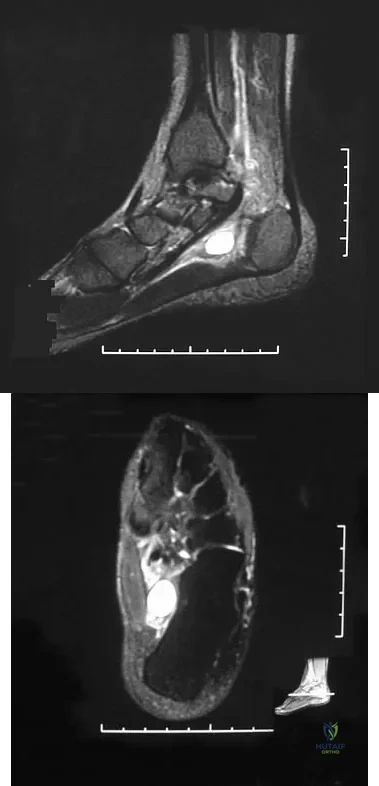

Question 25High Yield

A 32-year-old woman sustained an injury to her left upper extremity in a motor vehicle accident. Examination reveals a 2-cm wound in the mid portion of the dorsal surface of the upper arm and deformities at the elbow and forearm; there are no other injuries. Her vital signs are stable, and she has a base deficit of minus 1 and a lactate level of less than 2. Radiographs are shown in Figures 9a and 9b. In addition to urgent debridement of the humeral shaft fracture, management should include

Explanation

Question 26High Yield